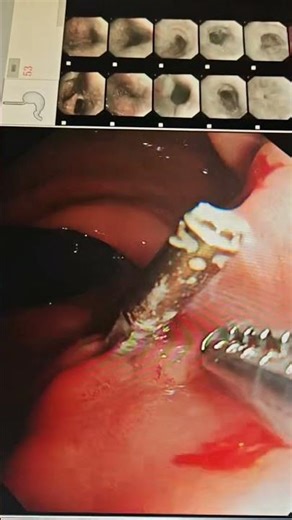

#Endoscopic Foreign Body Retrieval Procedure

Foreign Body Removal: Overview of Bronchoscopic Techniques

Endoscopic Foreign Body Retrieval Complications

Extraordinary Manoeuvre with Foley Catheter, in a Case of Foreign Body (Coin) Retrieval: Unusual Management of a Usual Presentation | SurgMedia

Endoscopic Foreign Body Removal Forceps || Dr.sun #endoscopy